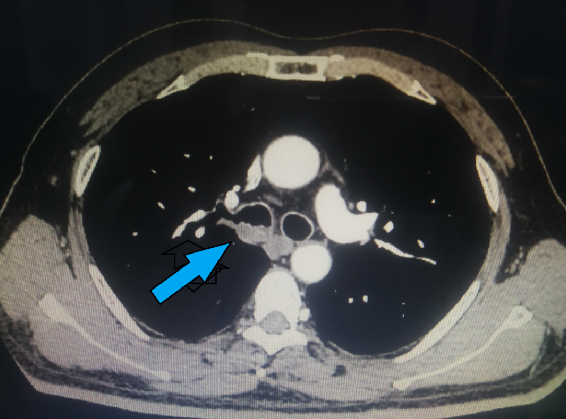

3月16日,辽宁省肿瘤医院副院长、胸外科刘宏旭主任、王伟主任及团队其他成员在麻醉科高浩然教授、手术室顾鑫和宋顺庆两位护士的配合下顺利完成一例非气管插管保留自主呼吸胸腔镜下袖式切除微创手术。随着年味逐渐散去,国内疫情形式逐渐明朗,医院就医的患者也逐渐的增多。在忙碌的工作中,我院胸外科刘宏旭教授团队始终坚持以患者生命健康为中心,在保证患者就医需求的基础上,一直紧跟着创新的步伐。3月16日完成的非气管插管保留自主呼吸胸腔镜下袖式切除微创手术,填补了我院乃至辽宁省在复杂中心型肺癌的微创手术区域的空白。       62岁的陈先生常年吸烟,1年前出现咳痰带血丝症状,当时未重视。近来出现呼吸困难,行胸部CT(见图1、2)检查提示右主支气管壁不规则增厚,可疑恶性;进一步行支气管镜(见图3)检查提示右肺上叶管口新生物,累及右主支气管开口及右肺二级隆突及中间干支气管,上界平隆突水平,下界距离中下叶开口约1cm,取病理提示鳞癌。  图1 图2 图3       面对这晴天霹雳,患者家属经过多方打听,了解到我们团队对于中心型肺癌的治疗有着丰富的经验并直接找到我们。经胸外科、胸内科、胸部放疗科、影像科和麻醉科共同会诊,专家们一致认为目前外科手术切除是最适合患者的治疗方案,但肿瘤位置高,单纯的支气管袖式切除不一定能达到完整切除的目的,很有可能需要隆突成形。考虑到手术当中气管吻合的难度及患者术后恢复,非气管插管麻醉方式比常规气管插管麻醉更具有优势。在保证肿瘤完整切除的前提下,本着对患者负责和对技术精益求精的心态,经充分的术前准备,于2021年3月16日成功行非气管插管保留自主呼吸胸腔镜下右肺上叶袖式切除、隆突成形、迷走神经部分切除重建、肺门纵隔淋巴结廓清术。(见图4、5、6、7)术中病理回报:气管上、下切缘净,这说明肿瘤切除彻底。       患者术后胸片见右侧余肺复张良好,气管镜见吻合口完整、通畅(见图8)。术后经过胡秀芬护士长领导的护理团队精心护理,给予患者快速康复和“无痛”优质护理,术后第1天下地活动,第3天拔除引流管,第4天恢复顺利出院。     图8       中心型肺癌病灶生长于肺脏根部,要想完整切除病灶,在多数情况下可能只有将单侧全肺切除,该手术方式无疑对患者造成了很大的伤害。支气管袖式切除术是将病灶连同被侵犯的支气管一同切除,再将正常的支气管两端切缘吻合。该手术方式是治疗中心型肺癌的标准术式之一,与单侧全肺切除比较,术后长期生存结果可与之相媲美,并更加有利于改善生活质量。非气管插管麻醉是术中使用不侵入气管的气道装置进行通气,保留患者自主呼吸,利用人工气胸达到单肺通气的效果。这种麻醉方式不仅能降低术后咳嗽等呼吸系统并发症,而且能缩短术后离床时间、禁食时间、住院时间及费用。胸腔镜手术技术凭借特有的优势(创伤小、手术视野好、术后恢复快)目前已被广泛应用,将胸腔镜下支气管袖式切除技术与非气管插管技术相结合,无疑可以进一步减少支气管袖式切除术的创伤,能最大限度地保护患者,更好的服务于患者。它的成功开展,标志着我院胸外科团队医疗水平达到了一个新高度。更重要的是,这种术式既避免了全肺切除术后治疗的困难,也最大程度上保留了患者的肺功能和最小限度下减少手术创伤,极大的改善中心型肺癌患者的生活质量。相信,辽宁省肿瘤医院胸外科将继续秉承“精诚•专业•仁爱 成就生命所托”的医院精神,不惧挑战,精益求精,砥砺前行,为更多患者提供更大的帮助。